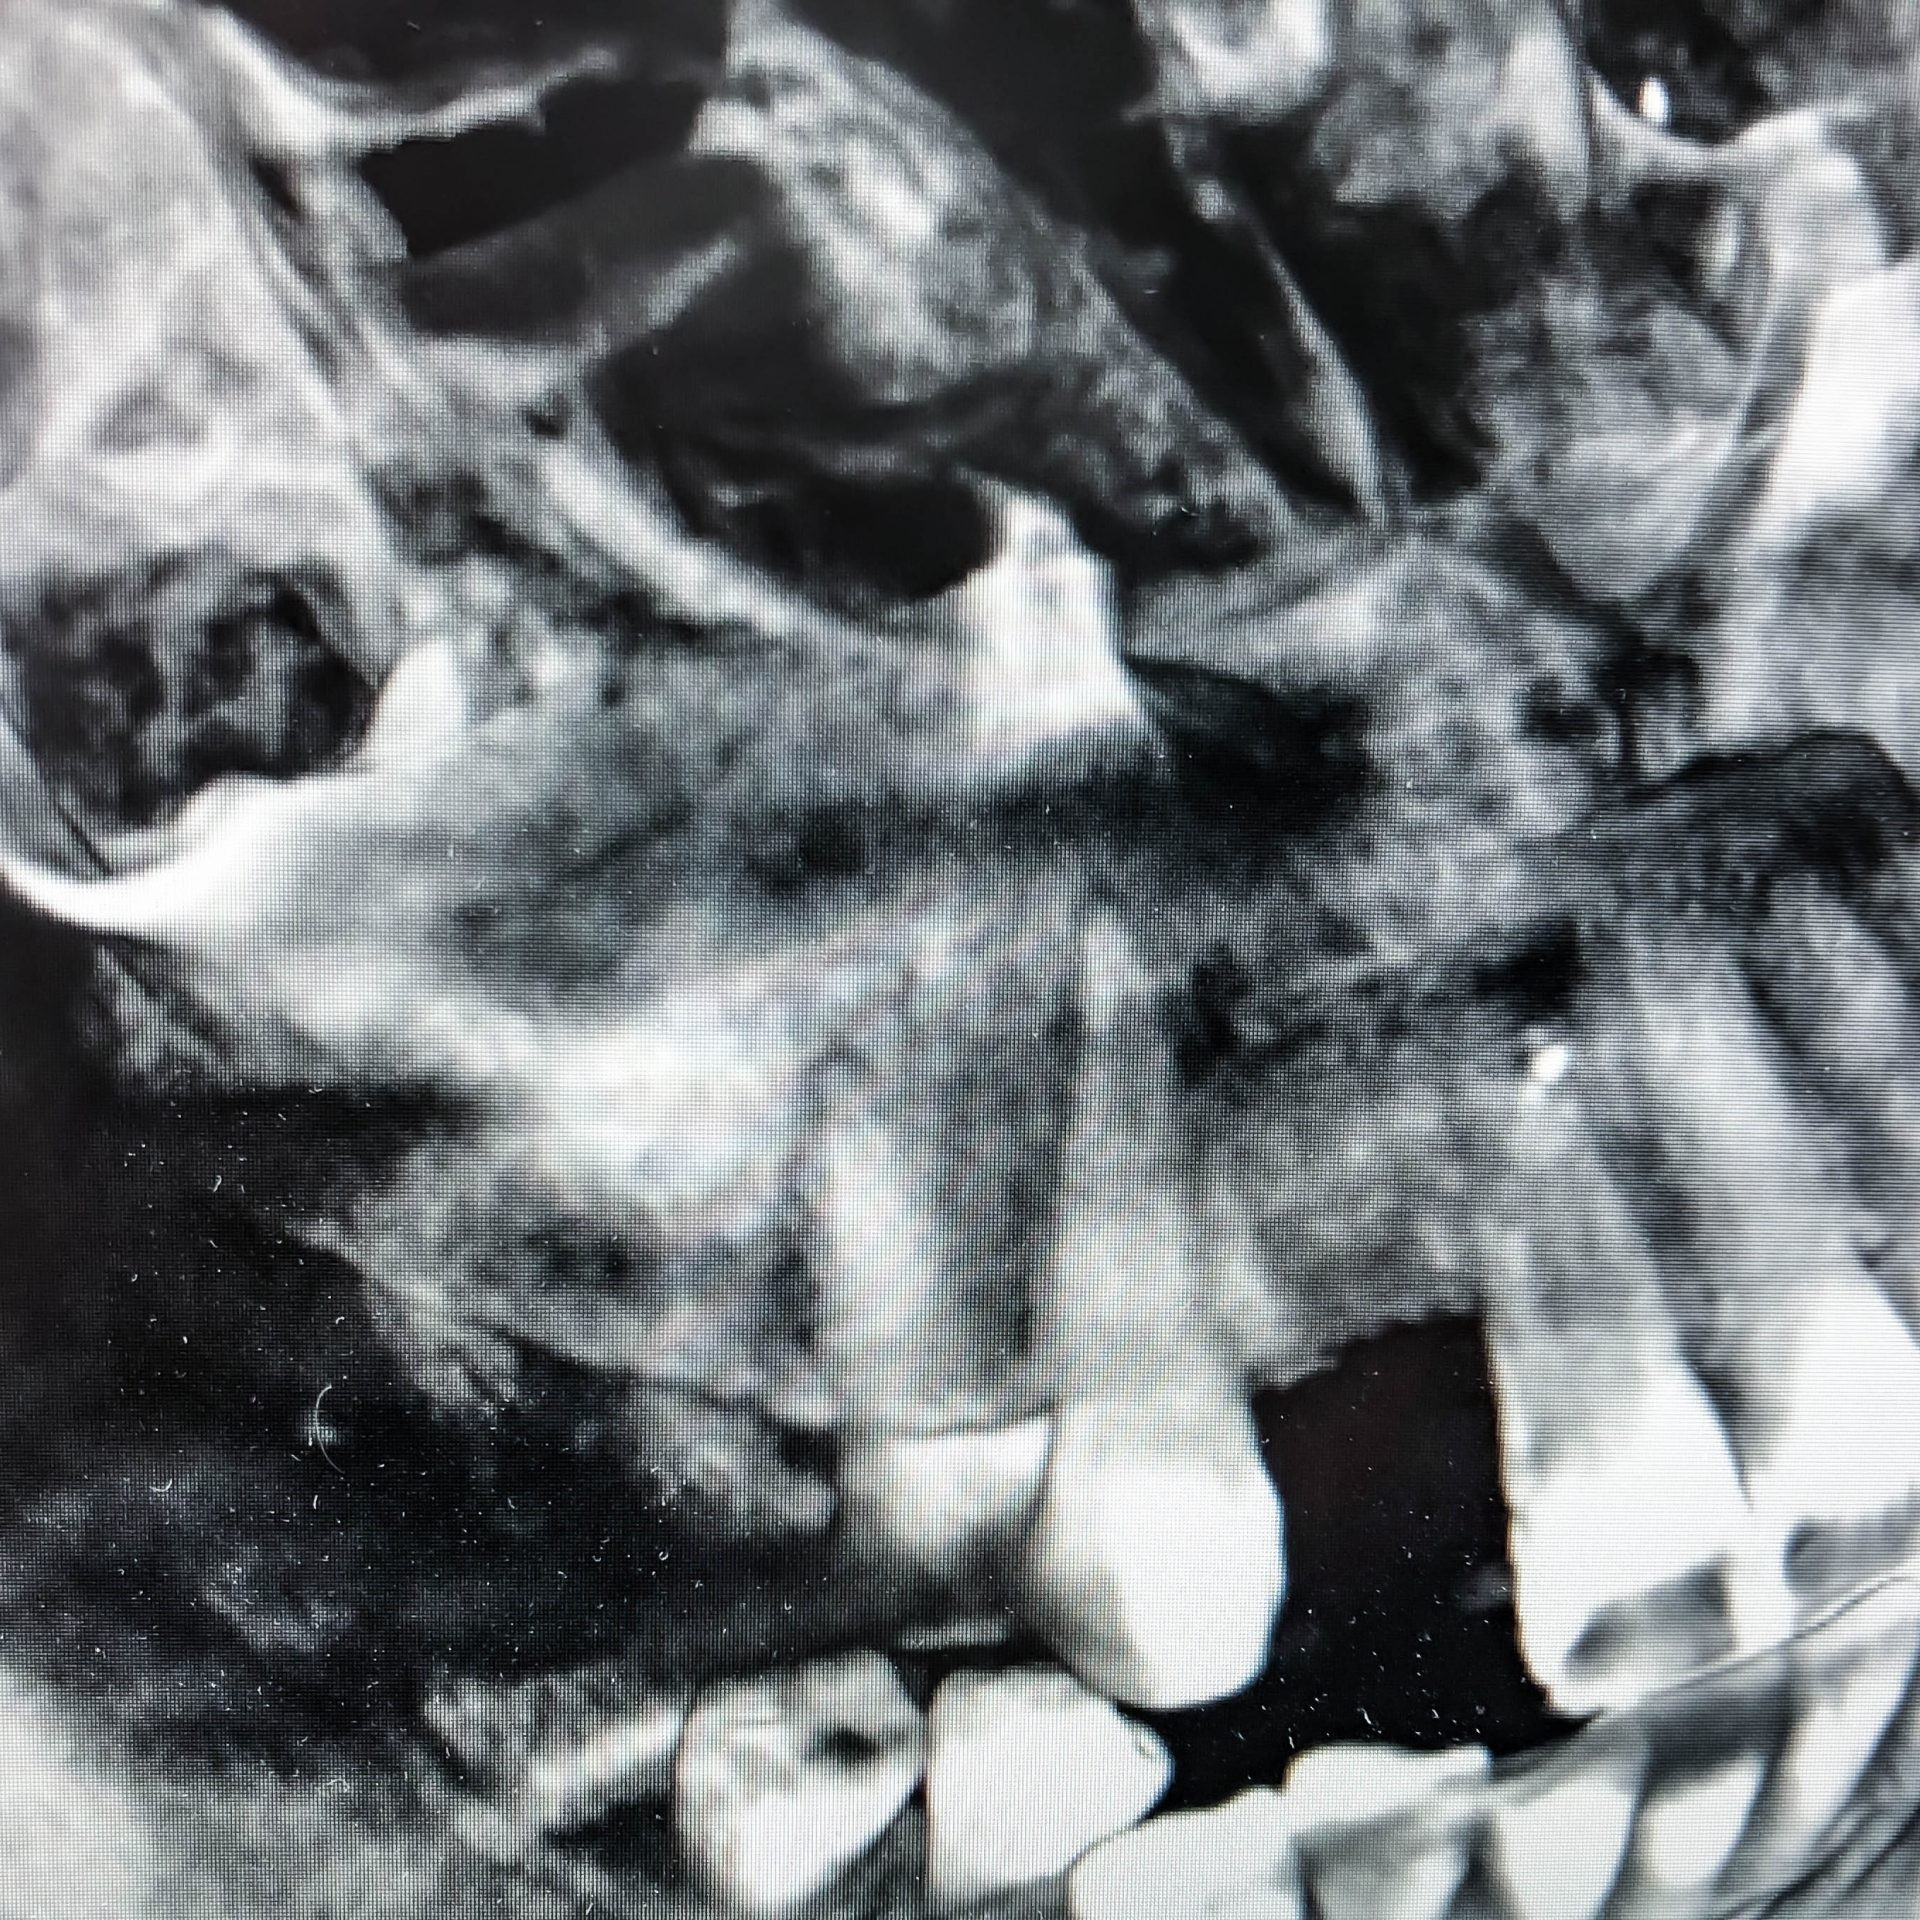

3D Röntgen DVT

Für radiologische Untersuchungen mit speziellen Fragestellung im Dental- als auch HNO- Bereich, bietet das DVT (digitale Volumentomographie) das genaueste Aufnahmeverfahren. Die 3D Röntgendarstellung kann sowohl zur Fokussuche bei Beschwerden, Wurzelkanalbehandlungen als auch bei chirurgischen Planungen genutzt werden. Für eine chirurgische Behandlungsplanung mit Implantaten ist dieses Verfahren der neueste Standard.